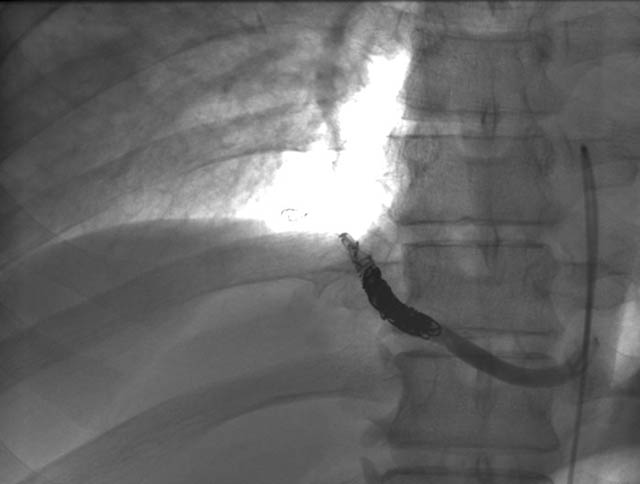

A previously healthy 43-year-old male presented with cough, fevers, and leukocytosis. A chest radiograph (Figure 1) revealed extensive consolidation in the right lower lung containing multiple cavities with air-fluid levels consistent with a necrotizing infection. A chest computed tomogram (Figure 2) showed an abscess cavity and consolidation in the right lower lobe with an aberrant blood supply from the descending aorta. This systemic blood supply was confirmed by subsequent 3D reconstruction (Figure 3). He was initially treated with IV antibiotics, resulting in normalization of his temperature and white blood cell count. He was then discharged home on a 3-week course of oral antibiotics. Three days prior to a planned surgical resection, he underwent angiographic localization of the feeding artery (Figure 4) and coil embolization (Figure 5).

Flexible bronchoscopy revealed normal bronchial anatomy (Video 1). There was no evidence of stricture. All segmental airways were present. A right thoracotomy was performed. The sequestration appeared as a bluish mass incorporated in the substance of the right lower lobe (Figure 6). The artery supplying the sequestration was visualized coursing through the inferior pulmonary ligament and divided (Figures 7, 8; Video 2). Alternating single and double lung ventilation, the sequestration was identified along the basolateral margin of the right lung (Video 3) with a clear line of demarcation. A combination of electrocautery and 4.8mm endoscopic staplers (Video 4) was used to separate normal lung from the sequestration (Video 5). Fibrin glue was applied to all staple lines. Normal bronchial airways were not divided and the remaining lower lobe inflated normally (Video 6). The post-surgical course was uncomplicated and the patient was discharged on post-operative day four. Pathology revealed parenchymal cyst formation with chronic inflammation and organizing pneumonia.